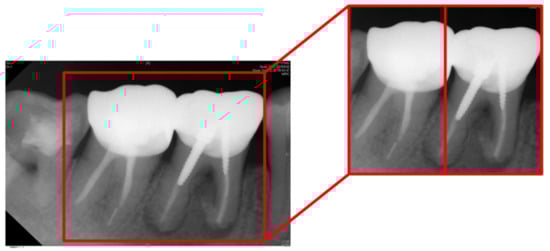

| Tooth Position in Figure 13 | Left | Right |

| Clinical Data | Normal | Lesion |

| This Work Before Enhancement | 90.91% Normal | 94.70% Lesion |

| This Work After Enhancement | 93.93% Normal | 97.35% Lesion |